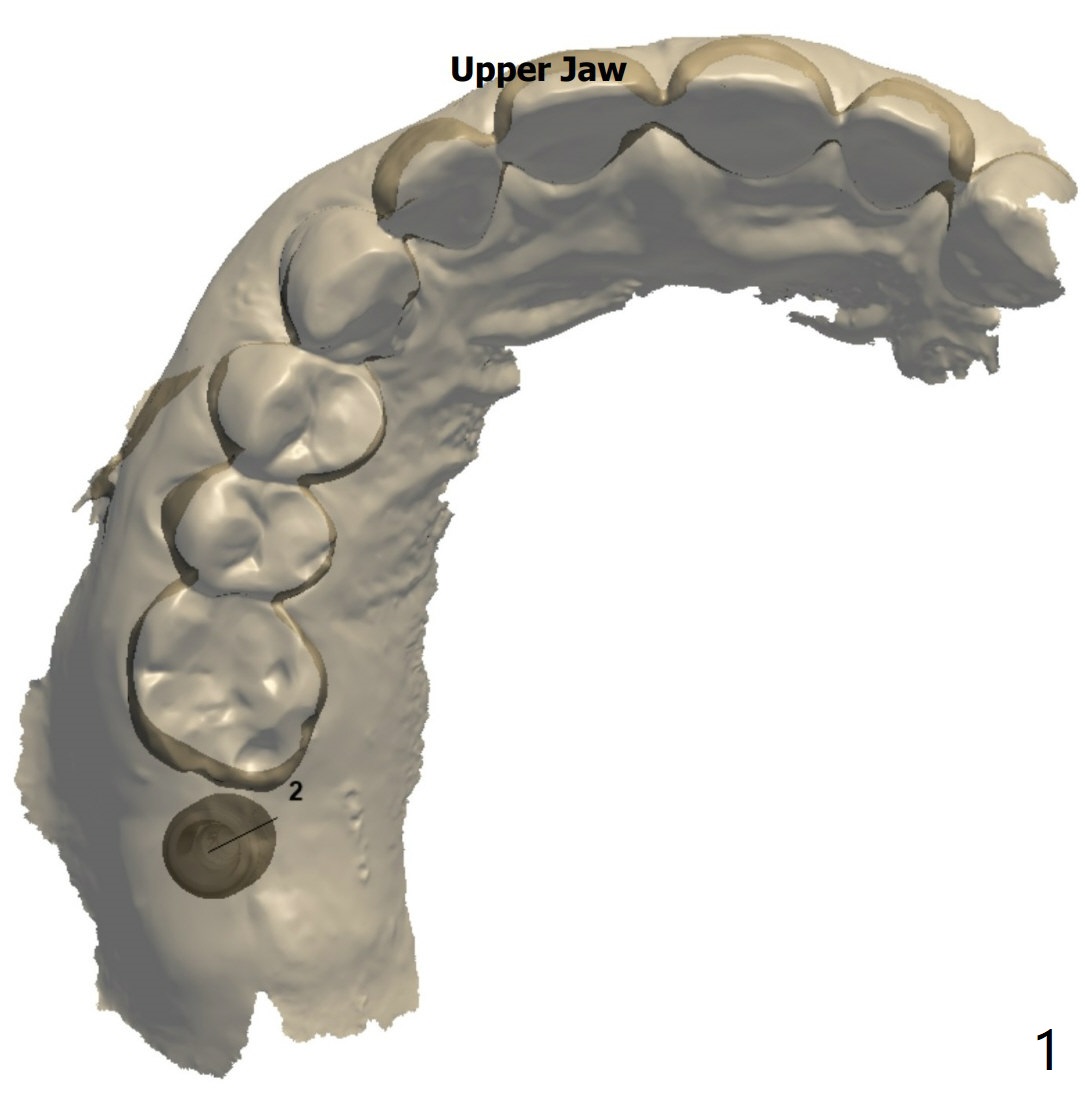

Short Fixture with Low Density

A 70-year-old woman

Return to Protect Graft  Oral Scanner